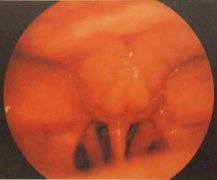

女性道人外生殖图片

女性外生殖器指生殖器官的外露部分,又称外阴,系指两股内侧从耻骨联合至会阴的区域,包括阴阜、大小阴唇、阴蒂、前庭、尿道口、阴道口及处女膜、前庭大腺、会阴等。